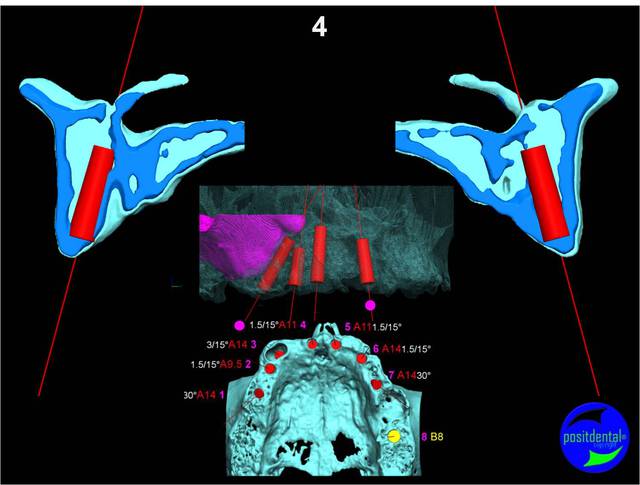

Extraction, pose d’implants Ankylos, pose des piliers Standard définitifs, mise en charge immédiate bi-maxillaire en une chirurgie.

Maxillaire supérieur – extraction 13, 26, 7 implants en MCI, 1 implant en MCR pose summeurs, densification par ostéotme, comblement osseux, bridge provisoire sans fausse gencive avec renfort métallique.

Maxillaire inferieur – extraction 35, 34, 44, 45, 6 implants MCI, comblement osseux, bridge provisoire sans fausse gencive avec renfort métallique.

en attendant la pano voici les coupes de la S.I.A.O.